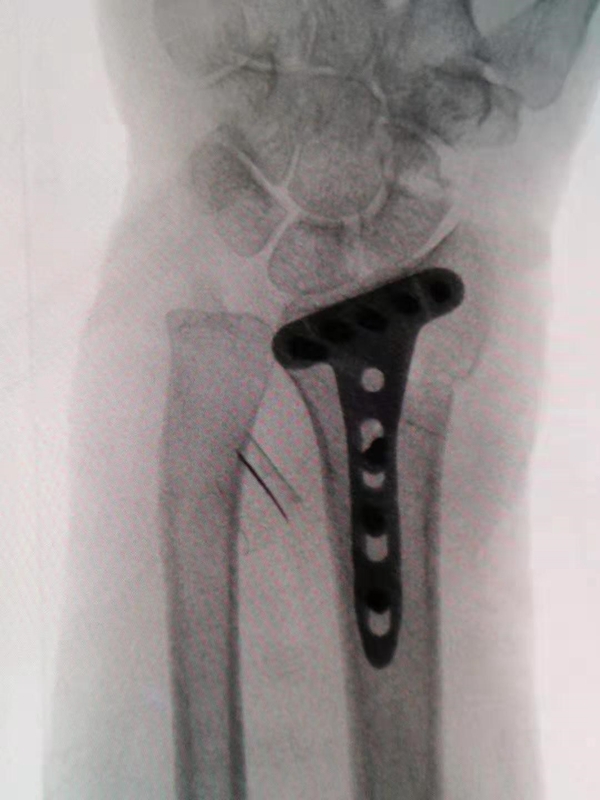

A、标准:螺钉的长度刚刚好到对侧皮质却不穿过对侧皮质,钢板高度刚好到分水岭又没有高于分水岭,螺钉角度紧贴关节面但又没有穿入关节。

F、由于掌侧端骨皮质较多,一般复位后先在远侧骨折块两侧打入2枚克氏针临时固定,直视及C臂透视确认掌侧复位满意后选择低切迹钢板或微型钢板固定。

如骨折块较小微型钢板无法有效固定,则选择掌侧低切迹钢板做掌侧“框架“固定,但放置高度不得超过“分水岭“解剖标志,对单纯桡骨极远端骨折涉及关节面但无明显塌陷病例,先前打入的2枚克氏针根据情况剪断后即可有效固定。

G、克氏针主要经钢板穿3个方向:月骨窝、桡骨茎凸及横向或纵向固定(适用于十分粉碎或下尺桡关节损伤的患者)。骨折越复杂应用的克氏针越多,如果与螺钉打架,则更换克氏针。

H、置放钢板的位置十分重要,要注意尽量靠近远端,但不能超过分水岭;一般放置在分水岭稍微靠近端2mm,若太远端虽然可以防止边缘的骨折移位,但则需要用万象锁定螺钉,调节角度打钉,否则很容易穿进关节。